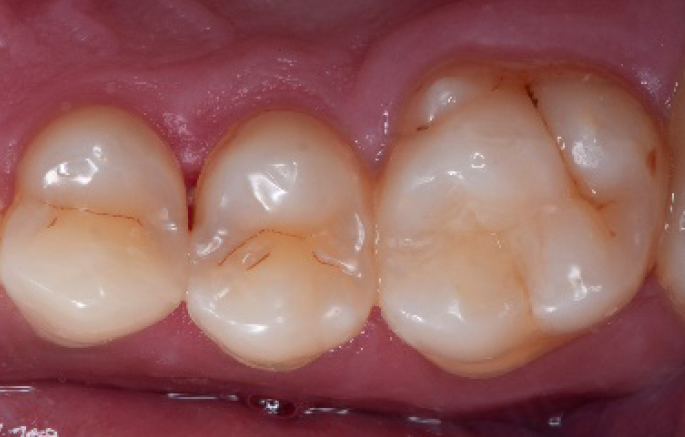

After

Final situation 2 weeks after the filling. Great comfort and no sensitivity at all were reported by the patient.

Step 11:

Occlusal surface restored using Spectra ST4 composite in shade A2.

Step 12:

The situation after rubber dam removal.

Step 13:

Occlusal check

Step 14:

2 weeks control